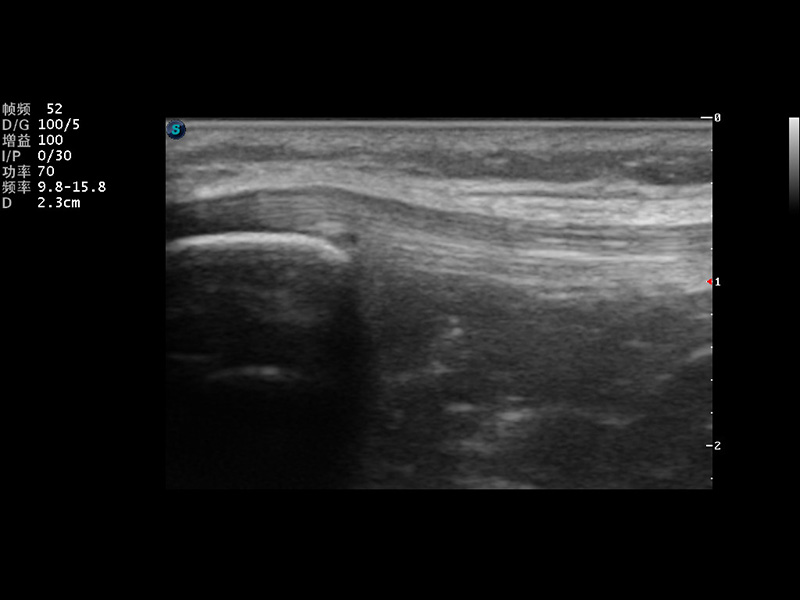

S9便携式彩色多普勒超声诊断仪是1xBET研发的高端便携彩超设备,外观设计新颖、产品性能卓越。S9在便携超声领域采用了突破传统的触摸屏交互设计,并以先进的软件硬件技术和设计理念,为您带来清晰的图像质量、稳定的工作性能和便捷的操作体验。

μ-Scan微米成像